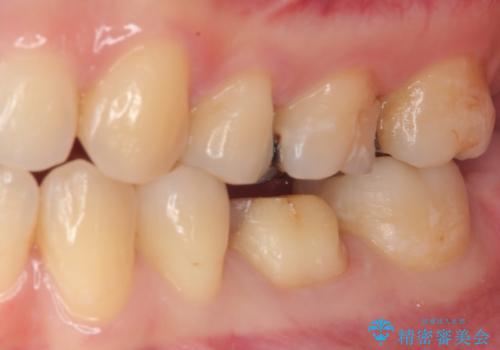

痛みやしみることもなく、適合もよく、機能的に問題もなく、見た目も満足されていました。

今後は他の金属の詰め物(メタルインレー)のところを治療していく予定です。